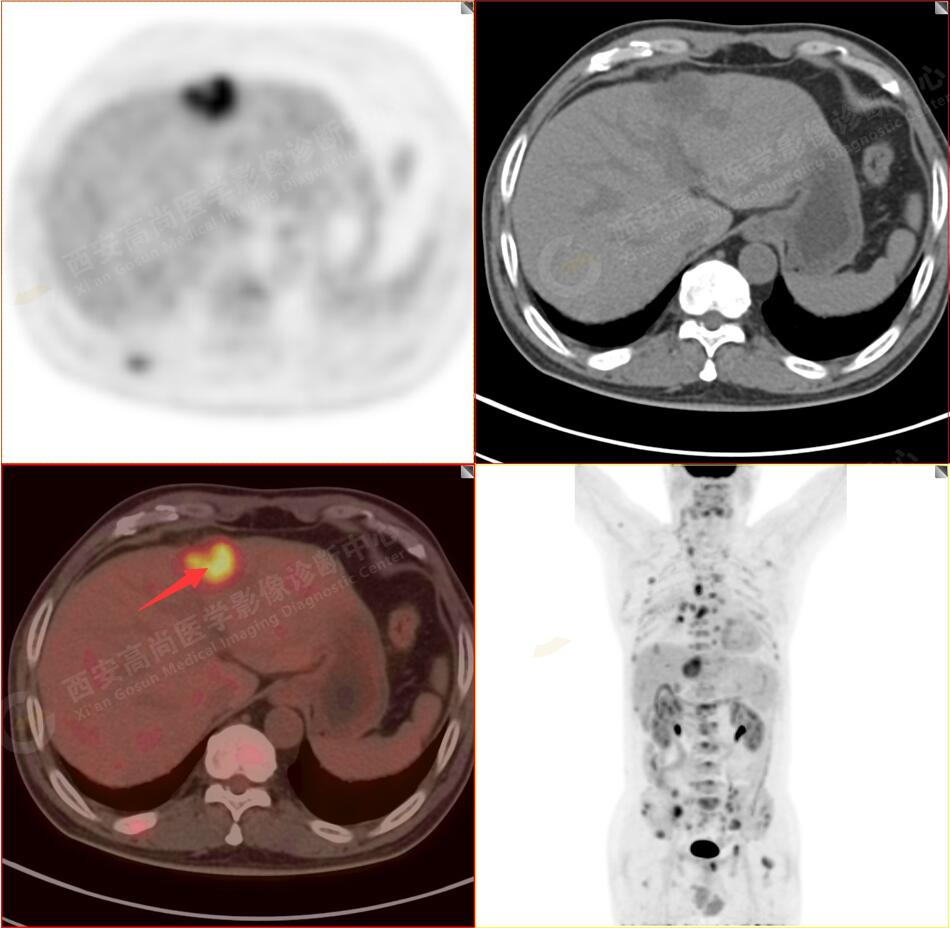

PET/CT圖像

2.以下為全身多發(fā)轉移灶

4.肝S4、8段團塊狀及結節(jié)狀低密度病變,以S4段病變?yōu)橹什煌潭菷DG代謝異常增高,考慮為肝多發(fā)轉移。